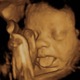

• 3D

3D

Kazunori Baba from Tokyo, Japan, first reported a 3-D ultrasound system in 1984 and succeeded in obtaining 3-D fetal images by processing the raw 2-D images on a mini-computer in 1986.

• 4D Ultrasound Video